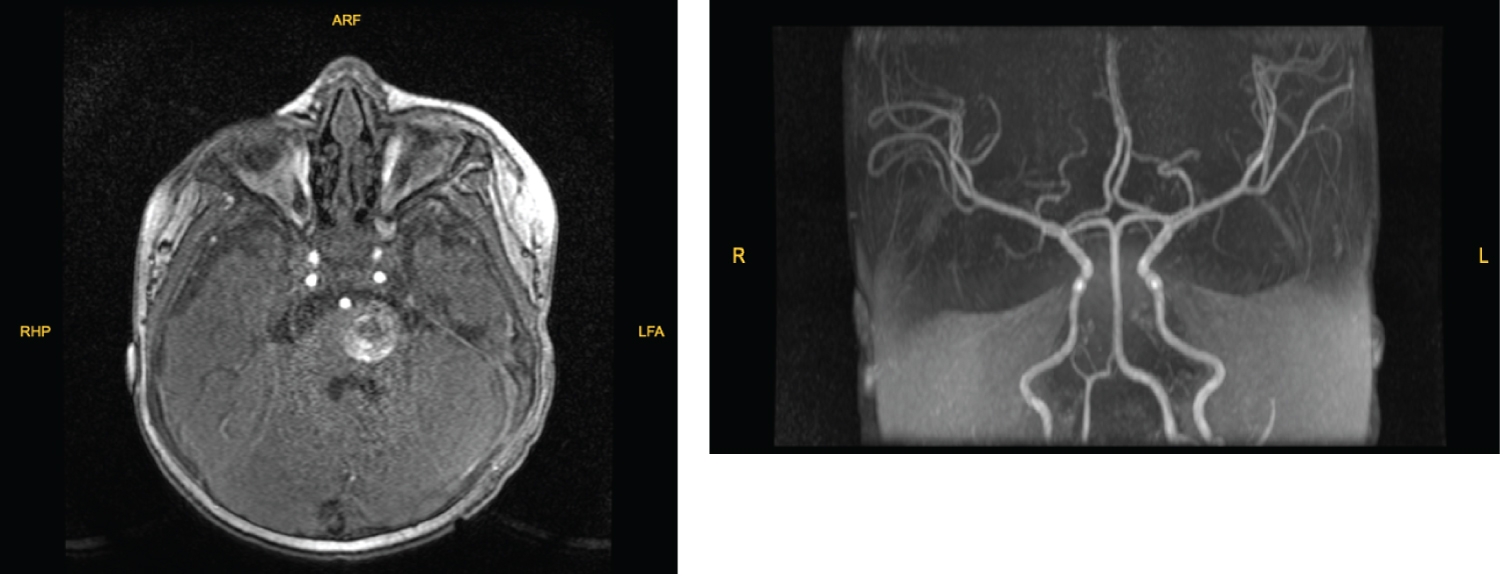

Blood tests were evaluated, and no pathologic value was seen. Magnetic resonance imaging (MRI) and angiography (MRA) was obtained which revealed a pontin mass along the dorsal aspect of the posterior fossa. The lesion is heterogeneously hyperintense on T1 and T2 weighted sequences (Figure 1 and Figure 2). The mass was well-circumscribed and heterogeneous, and evidence of previous hemorrhage within it. He was consulted to our department with preliminary diagnosis of pontine cavernoma and hemangioma. The differential diagnoses of an intracranial vascular lesion in this one year-day old infant included hemangioma, hemangioblastoma, vascular malformation, and other neonatal tumor types, such as soft-tissue sarcoma [8].

Figure 1: MR angiography showed a non-vascular lesion narrowing forth ventricle on the left part of pons. View Figure 1

Figure 4: Postoperative Day 30 control MRI, lesion was totally removed. T1, TOF and T2 flair sequences of MRI images. View Figure 4

On his post-operative day 12 we took sutures and no cerebral spinal fluid collection was seen. We planned a control magnetic resonance angiography and obtained in his post-operative day 30 (Figure 4). No residue lesion was revealed.